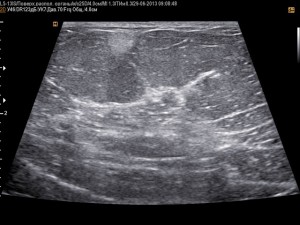

- УЗИ молочной железы.

Избыточное деление жировых клеток в структуре груди приводит к появлению плотного образования, которое по мере роста отделяется от других тканей и приобретает самостоятельную подвижную структуру. На УЗИ образование определяется как плотное однородное скопление клеток с четкими или размытыми контурами. Иногда его трудно разглядеть, даже если опухоль капсулирована и отделена от других тканей. Размеры жировика – от нескольких мм до нескольких сантиметров, что дает отрицательный косметический эффект и требует проведения операции по извлечению липомы.